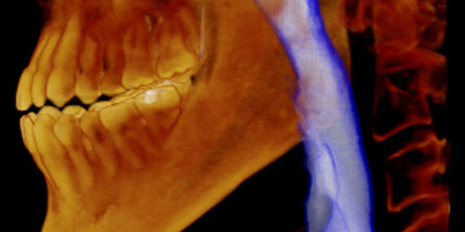

More detail, more confidence

70μm resolution @ 4x3cm

Image reconstruction in 6 seconds

Superior image processing technology